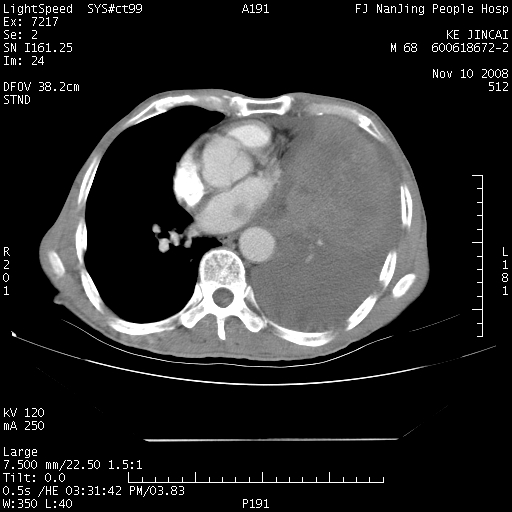

是个很有看头的病例,咋人气那么不旺?没多少人兴趣呢?这个病例几大怪:1   恶性肿瘤侵犯心肌左房怪,心肌一般不会被恶性肿瘤侵犯吧?2   左下肺均匀实变怪,内无含气,有别一般不张实变,含气肺泡完全为液体取代,而非一般不张实变的肺萎陷,冷不丁还以为是肿大的脾脏3   肿瘤本身怪,像tb肺不张4   这么有看头的病例没人气怪。呵呵。

左肺恶性肿瘤侵犯肺动脉,左心房内瘤栓,胸膜转移。

左肺恶性肿瘤侵犯肺动脉,左心房内瘤栓,胸膜转移,少见,学习了。